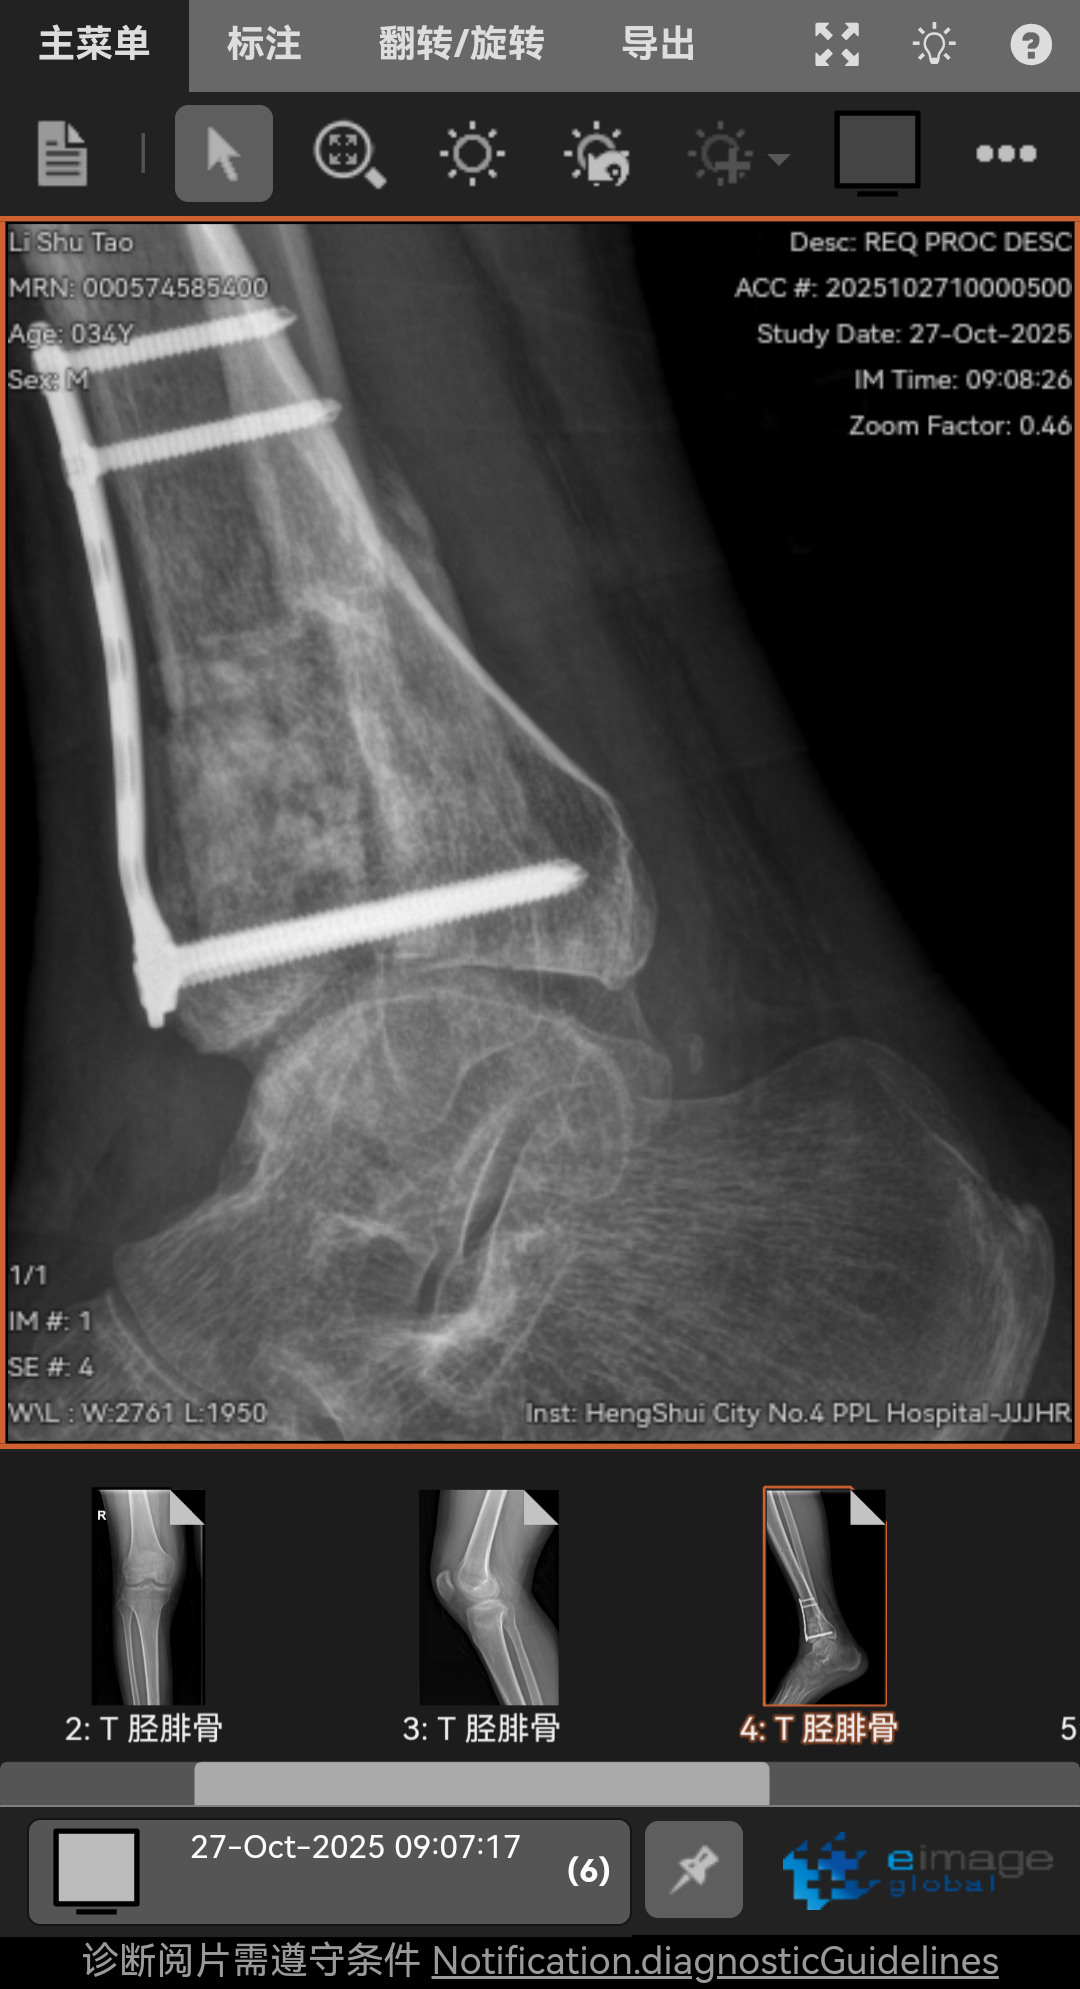

高坠骨折,6个月了,脚底板麻木,按压有刺痛,我是汗脚现在脚底板干燥,怎么办呢?走路腿特别沉重脚踝活动还不行,膝盖伸不直有点积液,怎么办呢!求求兄弟姐妹你们了。